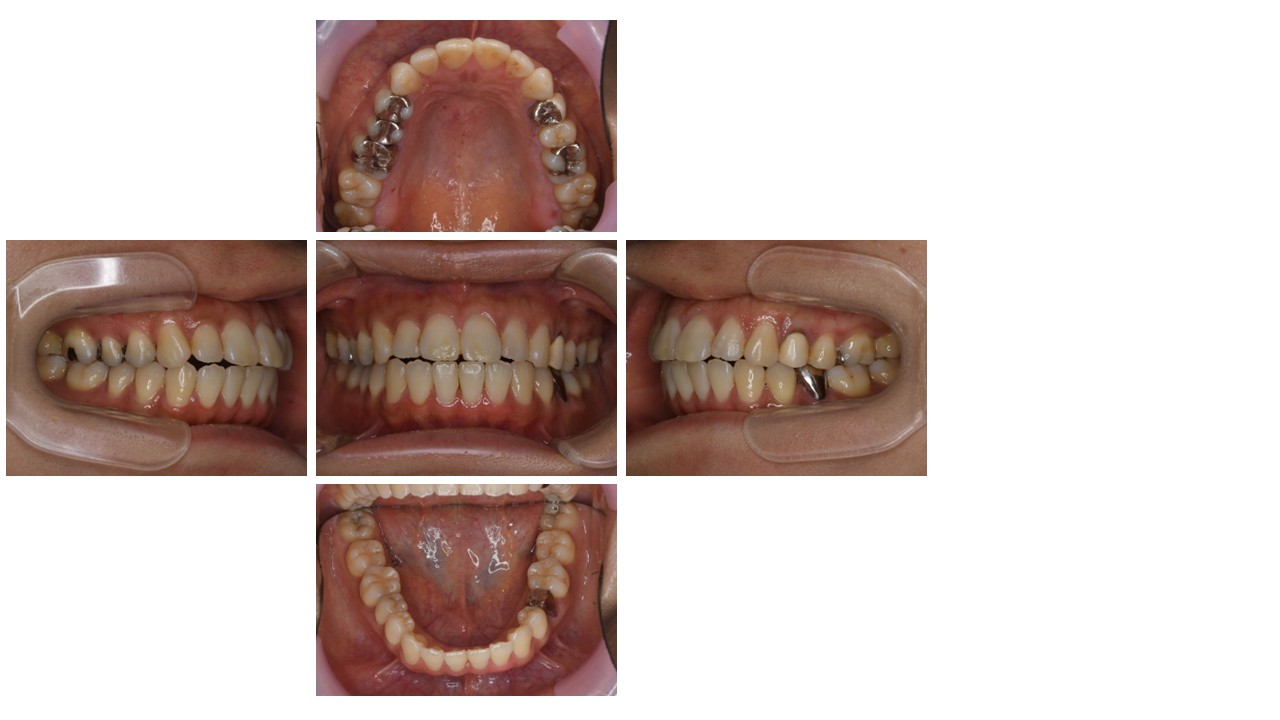

治療中